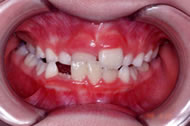

受け口を気にして来院された7歳の男子です。前歯部反対咬合症例として矯正治療を開始いたしました。上顎にリンガルアーチ、顎外にチンキャップを装着し前歯の咬み合わせを改善した後、成長終了を待って非抜歯で後期エッジワイズ治療に移行いたしました。後期治療に2年8カ月を要し治療費は前後期で90万円(税抜)となりました。このケースは早期に前歯のかみ合わせを改善できたため、良い治療結果となりました。

初診時